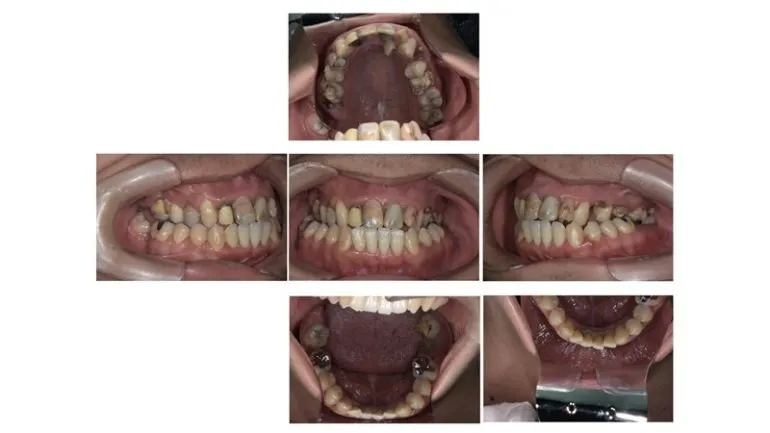

【症例2】

治療名

インプラント治療

治療説明

インプラント治療とその他の補綴物による修復を行いました。

治療期間

2年3ヶ月

副作用・リスク

手術中に神経や血管を傷付ける可能性があります。痛み、腫れ、出血があります。インプラントの初期固定が取れない場合は、治療期間が長引いたり、すぐに仮歯を入れることができない場合があります。

料金

¥3,905,000(税込)

インプラントのみ